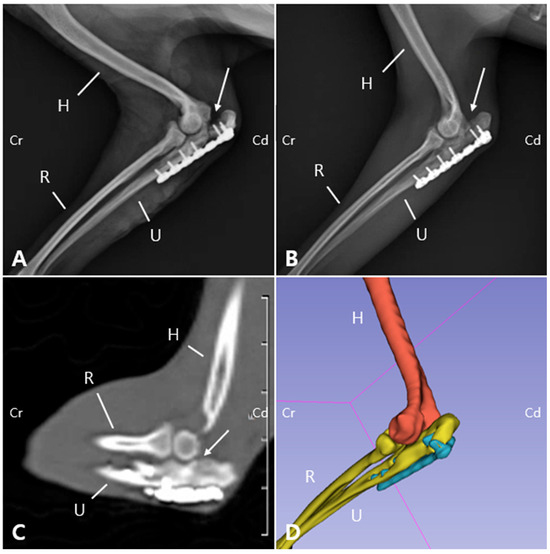

A six-year-old, neutered male Pomeranian weighing 4.25 kg was presented with a two-year history of non-weight-bearing lameness of the left thoracic limb following an untreated traumatic olecranon fracture. Orthopedic examination revealed markedly reduced elbow joint range of motion and muscle atrophy. Radiographs demonstrated [...] Read more.

A six-year-old, neutered male Pomeranian weighing 4.25 kg was presented with a two-year history of non-weight-bearing lameness of the left thoracic limb following an untreated traumatic olecranon fracture. Orthopedic examination revealed markedly reduced elbow joint range of motion and muscle atrophy. Radiographs demonstrated a distinct fracture line with proximolateral displacement of the olecranon fragment. Preoperative computed tomography (CT) and three-dimensional (3D) reconstruction were used to establish the surgical plan and to pre-contour a locking plate. Surgical treatment was performed in sequential steps, including removal of scar tissue, reopening of the bone marrow channel, and internal fixation. Considering the compromised biological environment of a chronic non-union, a bioactive graft composed of porous leaf-stacked structure (LSS) polycaprolactone particles incorporating recombinant human bone morphogenetic protein-2 (rhBMP-2) and mesenchymal stem cells (MSCs) was applied in combination with plate-screw fixation. The patient showed progressive improvement after surgery, achieving full weight-bearing and restoration of elbow joint motion comparable to the contralateral side. Follow-up radiographs and CT confirmed fracture union, and the radiolucency of the LSS scaffold enabled precise monitoring of bone healing. This case highlights the potential utility of combining patient-specific surgical planning with sustained delivery of rhBMP-2 and MSCs using LSS particles for the management of chronic non-union fractures in small animals. Full article

Figure 1